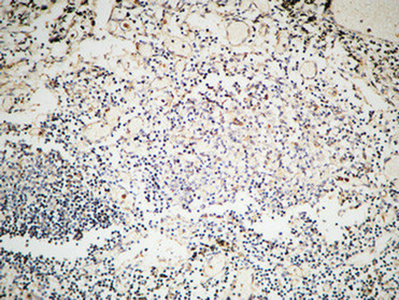

WB,IHC-P,IF-P,IF-F,ICC/IF,ELISA

稀释比(Dilution Ratio)

WB 1:500-1:2000, IHC-P 1:100-1:300, IF-P/IF-F/ICC/IF 1:200-1:1000, ELISA 1:20000.Not yet tested in other applications.